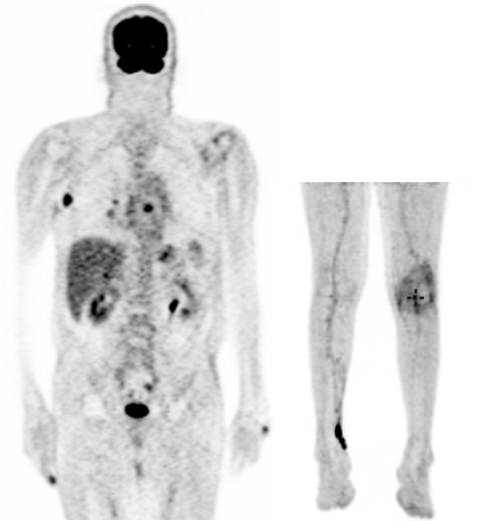

接獲該病例的馬偕醫院血液腫瘤科、癌症中心主任張義芳表示,患者76歲男性,罹患黑色素癌第四期,癌細胞轉移至淋巴結,腫瘤遍布手指頭、右膝窩、肝臟、肺臟及骨骼轉移,到醫院時身體十分虛弱,幾乎是臥床難以行走的情況,但求生意志堅定,家屬也希望積極治療,經醫療評估及說明後,適合為其施行免疫療法,治療後如今病人可以到公園散步。

黑色素癌第四期的患者經由正子攝影,原先癌細胞擴散全身多處(上圖),接受免疫療法之後,癌細胞明顯清除(下圖)。圖/馬偕醫院提供